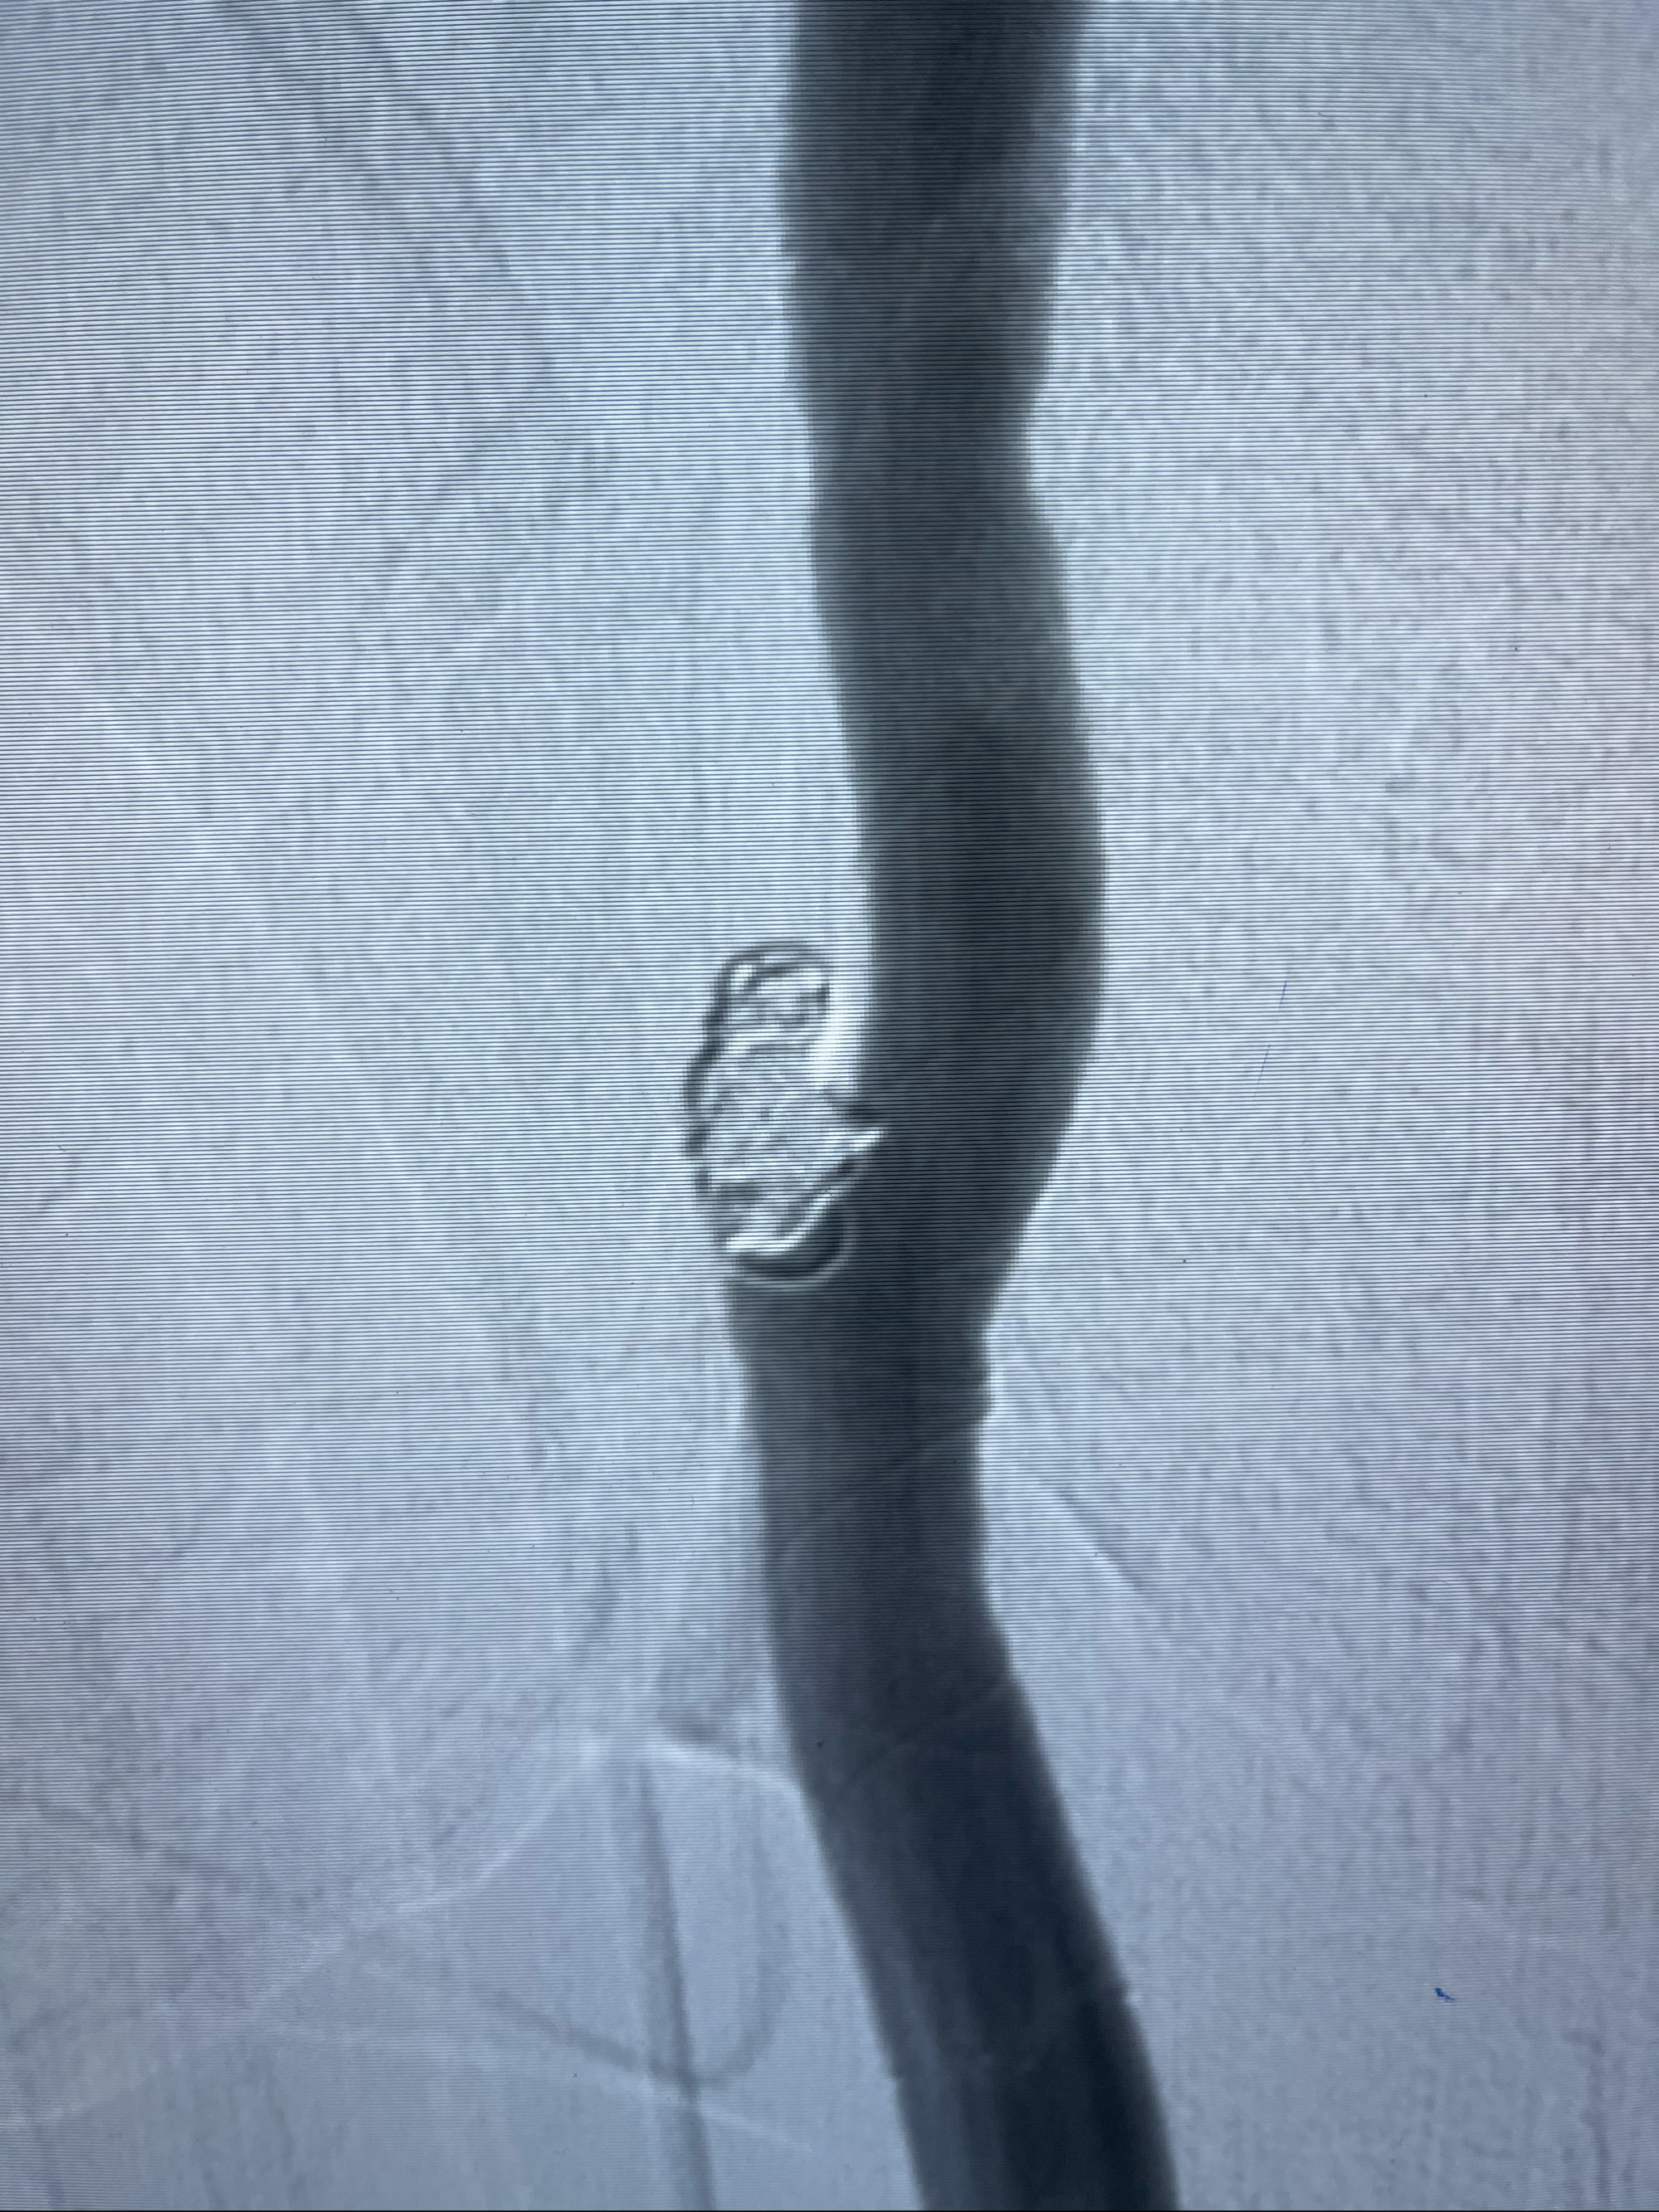

右侧颈内动脉夹层动脉瘤Lvis5.5-20mm支架辅助栓塞

即刻造影

术后即刻CT